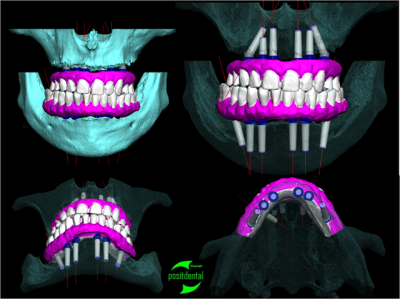

Je réalise l'ensemble, guide chirurgical de forage, positionneur d'implants et armature du provisoire à partir des images native DICON du scanner. Dans ce cas la chirurgie et la mise en fonction de la prothèse transitoire ont été effectuées en une opération.

Pour réaliser ce travail j'ai eut besoin du montage haut et bas sur cire.

1 je confectionne un guide radiologique.

2 après le scanner le patricien garde les planches et m'indique l'emplacement et le choix des implants et m'envoie le CD du dentascan

3 par e-mail je retourne l'étude avec des coupes, mise en situation et densité osseuse qui permettent d'évaluer la fixation primaire et la stratégie du forage

4 le guide, le provisoire, la reconstitution osseuse en stéréo lithographie, le tout fabriqué au labo puis livré avec un délai suffisamment nécessaire avant l'intervention pour être contrôlé physiquement et le guide inox stérilisé.

la réussite chirurgicale de cette intervention revient au Docteur Jean KOSKIEVIC (Paris).

posit